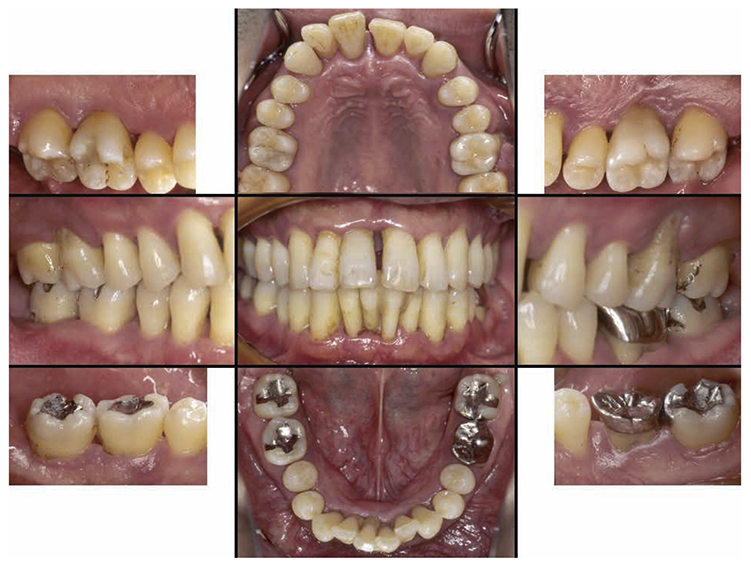

No obvious redness and swelling were present in the marginal gingiva across the full jaw; some blood congestion was however observed. The gingival shape of the anterior teeth in the mandible and maxilla was that of a thick shelf. Significant gingival recession was observed on the mandibular anterior teeth and the buckle side of the left and right maxillary first molar. The dental arch on the maxilla and mandible had a parabolic shape. Teeth separation was however observed between the maxillary central incisors, maxillary right central incisor and lateral incisor, maxillary right canine and first premolar, maxillary left canine and first premolar, and crowding was observed in the mandibular central incisors (Fig.1a).

At the time of first visit, the average PD (Probing Depth) on the full jaw was 4.5mm,maximum PD was 10.0mm, 43.5% had PD of 3mm or less,38.7% for 4-6mm,17.9% for 7mm or above. The average BOP (Bleeding on Probing) on the full jaw was 42.3%,teeth mobility on 17,22,23,32,33,41,46 was grade 1,grade 2 on 11,12,21,and grade 3 on 16,24,26,31 (Miller classification). Additionally, grade 1 on 36,16(mesial, distal),26 (mesial, distal) and 36,grade 2 furcation involvement (Lindhe & Nyman classification) was observed on 47. The plaque score at the first visit (O’Leary’s Plaque Control Record:PCR value) was 83.9%, which indicated poor oral hygiene status (Fig.1b).

At the first visit, the findings showed moderate to advanced horizontal alveolar bone resorption in the entire jaw, and advanced vertical bone resorption on 24,36,46, 47. Additionally, on 46,47 were radiolucent findings that were likely associated with furcation involvement, and radiolucent areas on the alveolar bone surrounding the root apex were shown on 16,11,26. Furthermore, distally on 47, radiolucent findings showed caries extending into the dental pulp.(Fig.1c).

Fig 1a

(Fig.1a) Intraoral photo taken during first visit (June 2007)